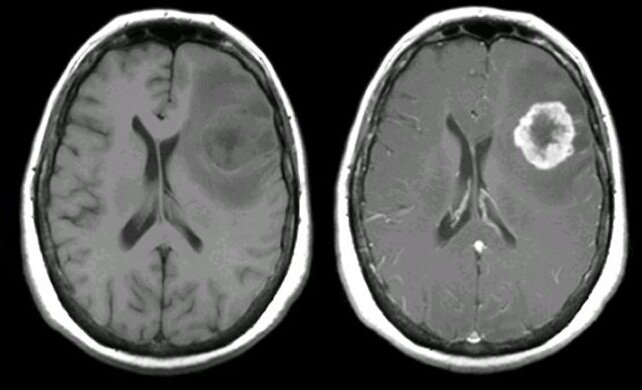

Т1 ВИ (читается "тэ один вэ и") - режим сканирования, который используется всегда и везде. Свободная безбелковая жидкость (например ликвор в желудочках мозга) на таких изображениях выглядит тёмной, мягкие ткани имеют различные по яркости оттенки серого, а вот жир ярок настолько, что кажется белым. Также на Т1 ВИ очень яркими выглядят парамагнитные контрастные вещества, что и позволяет использовать их для визуализации различных патологических процессов.

Слева - Т1 ВИ, а справа - Т1 ВИ после введения контраста. Опухоль накопила парамагнитный контраст. Просто и красиво!

А ещё на Т1 яркой будет выглядеть гематома на определённых стадиях деградации гемаглобина.